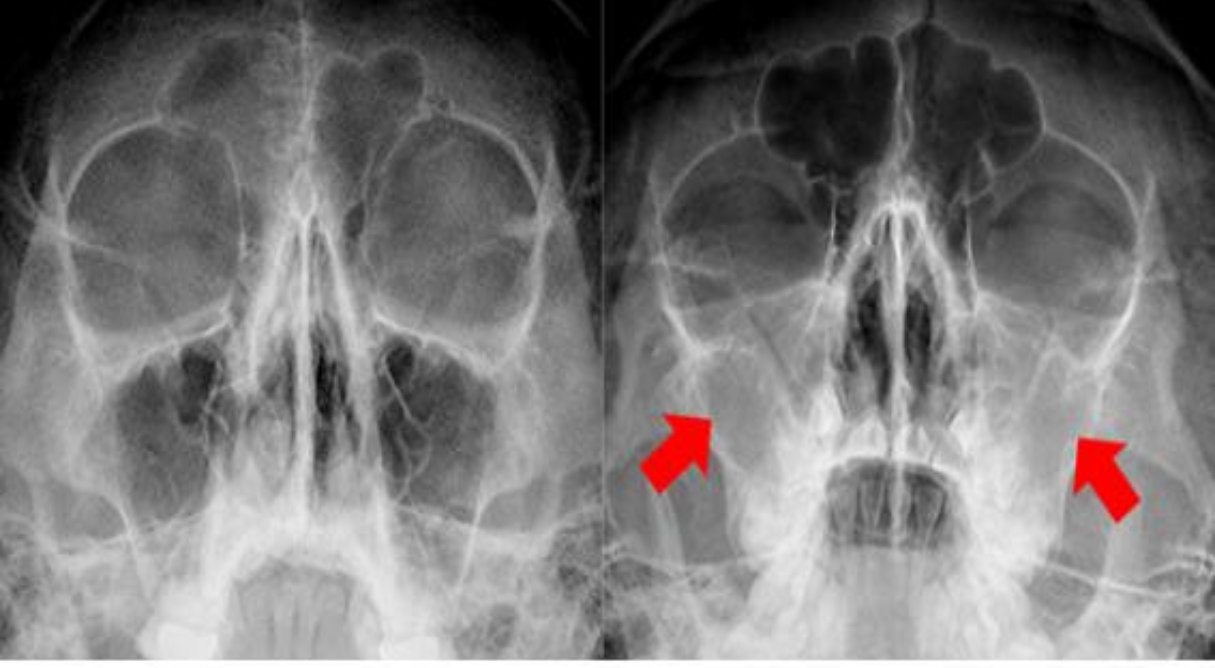

- 내시경 검사: 코 안으로 내시경을 넣어 비강과 부비동의 내부 상태를 직접 확인합니다. 육안으로 종양의 유무나 형태를 파악하는 데 유용합니다.

- 영상 검사: CT(컴퓨터 단층 촬영), MRI(자기공명영상) 등을 통해 종양의 크기, 위치, 주변 조직 침범 여부 등을 상세하게 파악합니다. 특히 암의 진행 정도를 평가하는 데 필수적입니다.